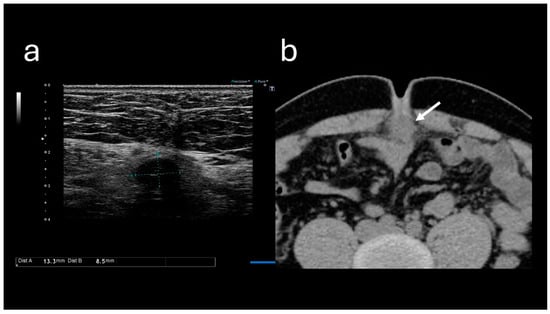

Blood test results revealed the following: white blood cell count, 10,500/μL; hemoglobin level, 14.7 g/dL; platelet count, 23.7 × 104/μL; blood urea nitrogen level, 13.7 mg/dL; creatinine level, 0.91 mg/dL; and C-reactive protein level, 0.74 mg/dL (Table 1). These results indicated mildly elevated inflammation marker levels; however, they did not indicate hepatitis, cholecystitis, or pancreatitis. Abdominal ultrasound sonography (A-US) revealed a low-echoic lesion of approximately 10 mm just below the umbilicus. Abdominal computed tomography (A-CT) revealed a soft tissue image below the umbilicus (Figure 2).

Figure 2. Images obtained at the time of the initial visit. (a) Abdominal ultrasound sonography reveals a low-echoic lesion of approximately 10 mm just below the umbilicus. (b) Abdominal computed tomography reveals a soft tissue mass located below the umbilicus (arrow).